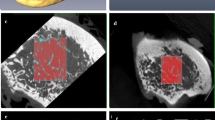

Texture analysis is an image processing method that aims to assess the distribution of gray-level intensity and spatial organization of the pixels in the image. The purpose of this study was to investigate whether the texture analysis applied to cone beam computed tomography (CBCT) images could detect variation in the condyle trabecular bone of individuals from different age groups and genders.

The sample consisted of imaging exams from 63 individuals divided into three groups according to age groups of 03–13, 14–24 and 25–34. For texture analysis, the MaZda® software was used to extract the following parameters: second angular momentum, contrast, correlation, sum of squares, inverse difference moment, sum entropy and entropy. Statistical analysis was performed using Mann–Whitney test for gender and Kruskal–Wallis test for age (P = 5%).

Texture analysis proved to be useful to discriminate mandibular condyle trabecular bone between genders.